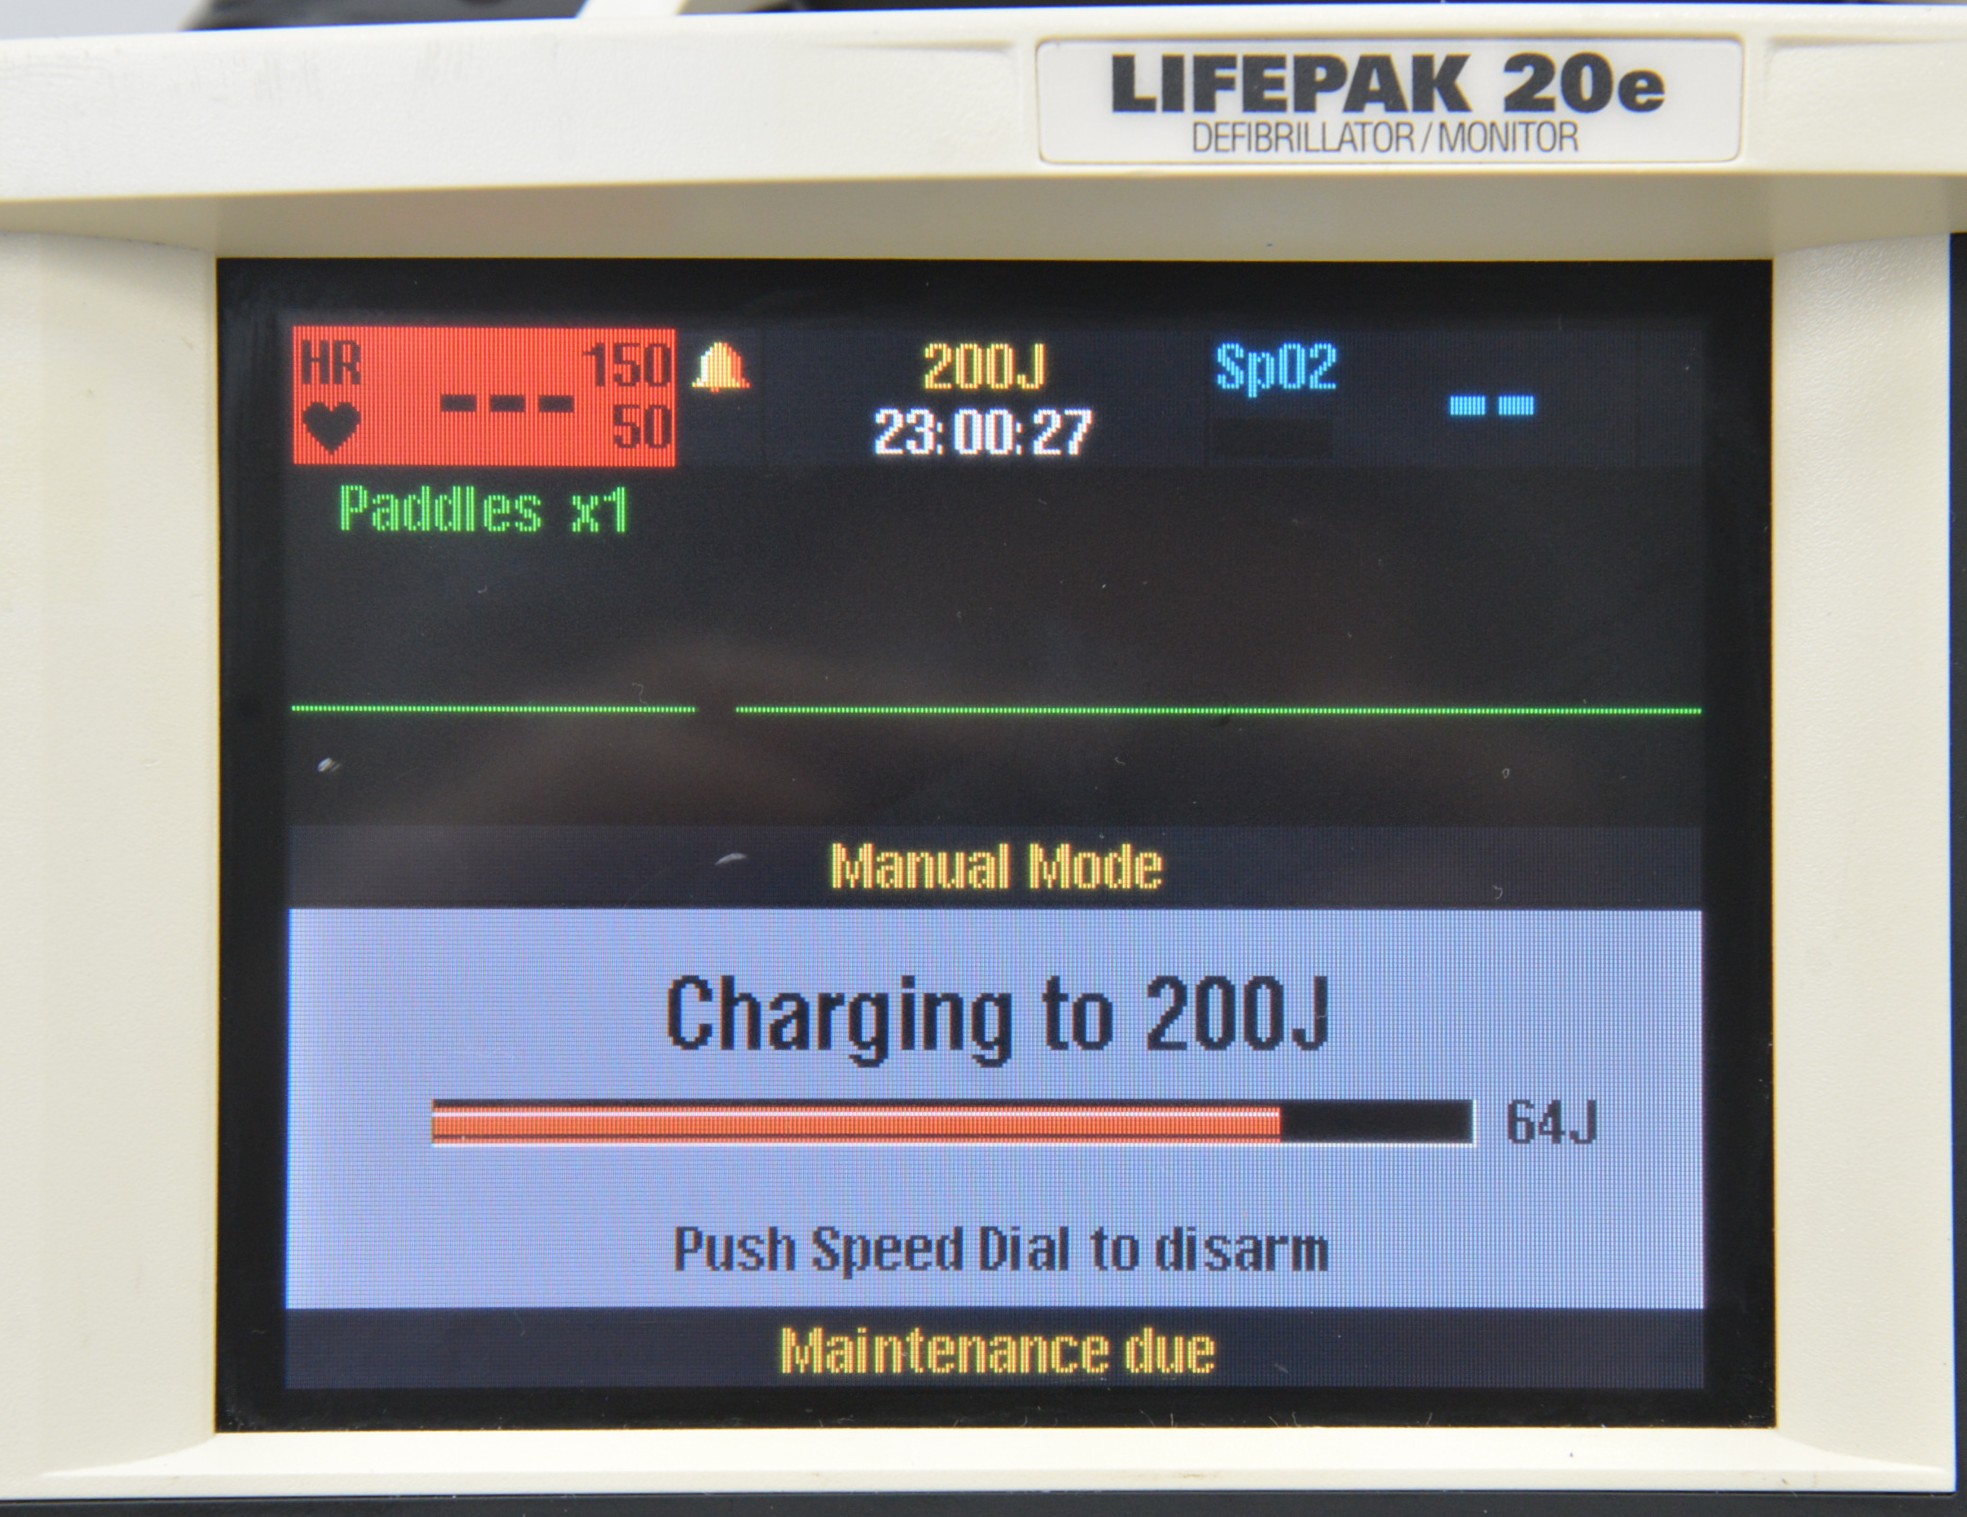

This Medtronic Lifepak 20e Defibrillator Monitor 2010 W/ Paddles is in good working condition. The unit powers on properly and responds to selections. All connection points are clean and in good condition. There are some scuff marks from previous use (see photos). This unit comes with a 30 day satisfaction guarantee. Includes everything in the pictures and nothing else.